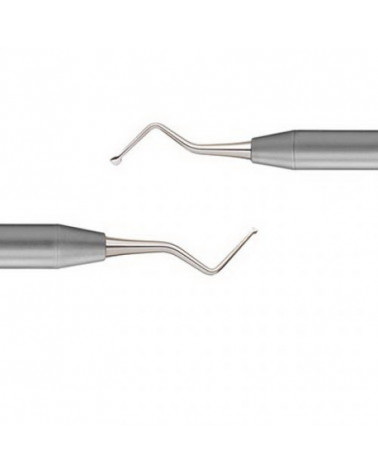

Пародонтальний ніж Nanos A застосовується для супраперіостального розсічення апікально та латерально під час тунелювання та хірургічних втручань на м'яких тканинах. Цей інструменти також корисний у створенні часткового або повного товстого клаптя конверта під час процедур трансплантації сполучної тканини в періопластичній хірургії та імплантації. Пародонтальний ніж Nanos A також дуже ефективний при піднятті клаптя в лінгвальній зоні і зоні піднебіння під час хірургічної операції.